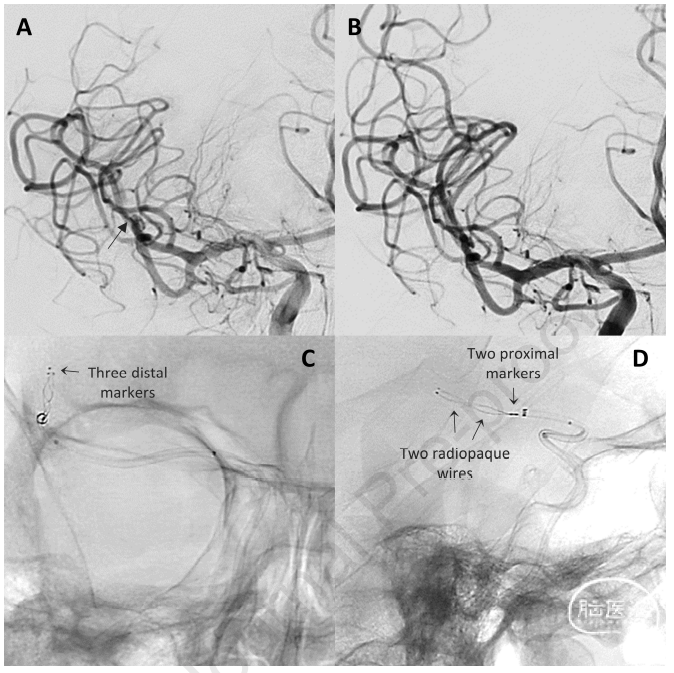

图2. 造影示右侧M2闭塞(A如箭头所示),使用AP17 2.5/28mm进行取栓,一次获得3级再通(B),患者症状从NIHSS 17分降至1分。非减影下AP17可以看到非透线的轮廓(C,D)。

图3. A. 造影示右侧M1闭塞,mTICI 0级。使用常规APH 6/40mm进行取栓,成功再通M1段,复查造影示血栓异位至双侧A2段。B. AP17 2.5/28mm用于右侧(C)和左侧(D)的取栓。左侧大脑前动脉取栓1次获得完全再通,右侧12段AP17取栓2次仍闭塞。(E)使用常规APH 6-40mm进行补救,结果意外解决,近端位于A1段(F. 如箭头所示)。解脱的APH留在原位,同时予动脉替罗非班。复查造影示右侧大脑中动脉及双侧大脑前动脉通畅(F)。没有临床后遗症。